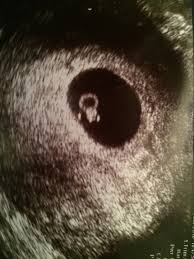

Miscarriage In Toilet - Lillis Tuckerman On Twitter Miscarriages And Toilets Cw Graphic Thread About Miscarriages Incredibly Sensitive Topic I Know I Ve Been There Do Women Really Suffer Miscarriages In Public Toilets Or Is This, In some cases, miscarriage can occur before you know you're pregnant.. The is very common in women that have a miscarriage at 6 weeks pregnant. You may look to see what has come away and you might see a pregnancy sac and/or the fetus, or perhaps something that you think might be the fetus. Miscarriage is one of those things that sits in the back of a woman's mind during pregnancy, and it's a fair concern given that the rate of miscarriage can run anywhere from 10% to 20% among women who know they are pregnant. If a few weeks go by on the watchful waiting plan, you can always go back to your clinician's office and opt for the medication or suction or d&c option. Woke up to bright red blood in the toilet.

Miscarriage I Just Felt Like It Was My Fault Bbc News from c.files.bbci.co.uk The truth is if you are 6 weeks pregnant with big blood clots from your vagina. This was also very similar to the miscarriage experience i had just read about. I was sent home to let the miscarriage finish itself. Miscarriage | 575.5m people have watched this. It is dangerous for the woman's health and requires immediate medical care. In a miscarriage that happens beyond 6 weeks, more tissue will be expelled. Recognize the symptoms of a septic miscarriage. For other women, the first signs of miscarriage are spotting or bleeding, followed by cramps in the lower back or abdomen.

This is because a baby is thought to have a good chance of surviving if they are born alive at 24 weeks. The pregnancy is definitely miscarrying, but only some of the pregnancy tissue has passed. More blood, like a light period. However, in others, vaginal bleeding may be so severe with clots coming out of your vagina. I've had 3 miscarriages (15 weeks, 7 weeks, and 9 weeks), and they were all different and difficult. A little more blood but still minima. The truth is if you are 6 weeks pregnant with big blood clots from your vagina. Watch short videos about #miscarriage on tiktok. There is no right way to miscarriage or grieve. My twelve week miscarriage story author: After a miscarriage it is common to feel guilty and to blame the miscarriage on something you have done, or failed to do. Miscarriage | 575.5m people have watched this. I'm so sorry for your loss.

Any Experience With Miscarriage Graphic Image Alert May 2020 Babies Forums What To Expect from images.whattoexpect.com There is no right way to miscarriage or grieve. If you miscarry at home or somewhere else that's not a hospital, you are very likely to pass the remains of your pregnancy into the toilet. After a miscarriage it is common to feel guilty and to blame the miscarriage on something you have done, or failed to do. A miscarriage may cause bleeding, cramping, and a sudden decrease in pregnancy symptoms. I finished my miscarriage on the toilet. Remove the contents of the miscarriage kit. The expelled tissue usually resemble large blood clots. Red spotting all day but only used 1 ultra thin liner.